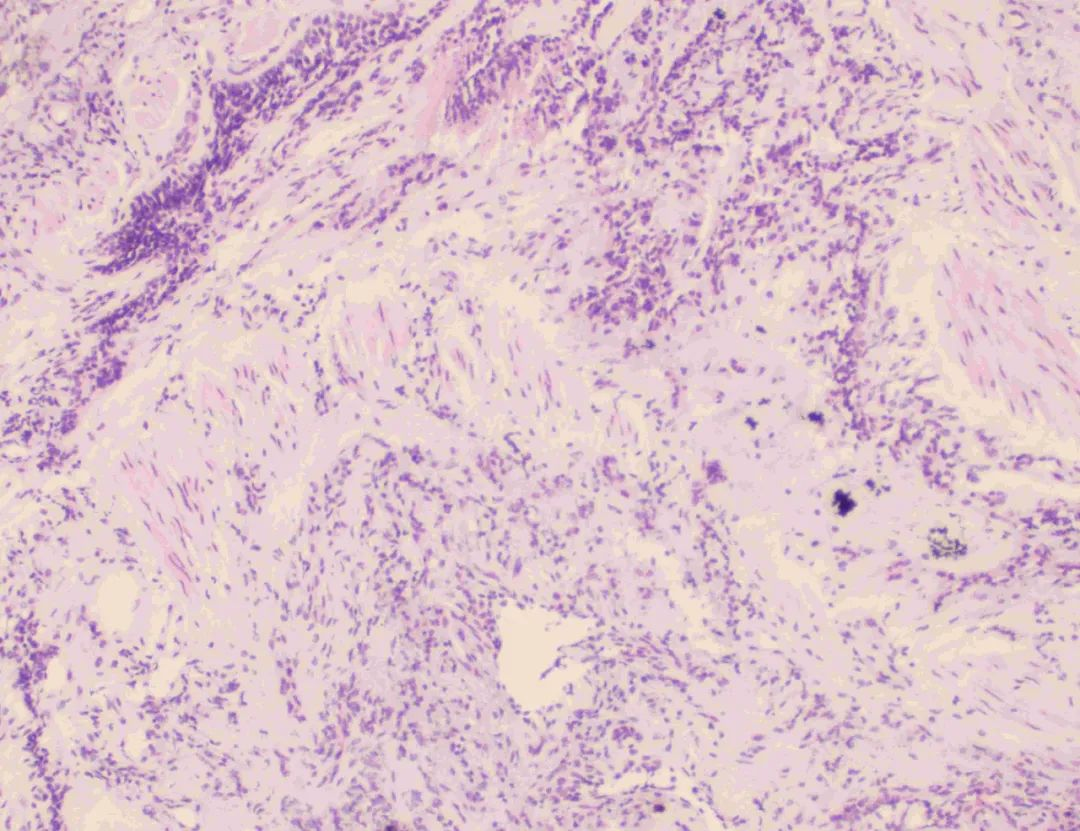

对冷冻肺活检术的必要性和并发症充分知情后,患者及家属签署同意书,罗少华主任带领学科团队在手术室全麻下为患者成功实施了TBCB,取得肺组织标本,术中出血少,患者未出现气胸等并发症,术后恢复良好,经病理确诊为寻常型间质性肺炎,为患者制定精准治疗方案提供了重要的依据。

肺活检组织病理